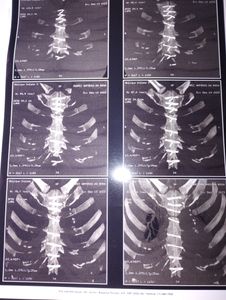

Eu Juarez estou fazendo essa vaquinha para arrecadar dinheiro para fazer 2 cirurgias de deslocamento nas retinas e também para ajudar a minha recuperação de 2 Infartos que deixou sequelas, estou perdendo a visão e também não posso sair de casa pois meu lado esquerdo está esquecendo.Quando faço esforço o lado esquerdo para de responder eu desmaio.Quem puder ajudar fico agradecido 🙏🏻